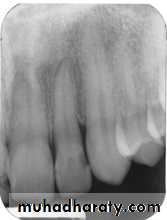

The bitewing radiograph is the view of choice for the evaluation of periodontal disease.

In addition to the periapical radiograph with paralleling technique could be used also, to evaluate the height of crestal bone is accurately recorded in relation to the tooth root.

The normal alveolar crest lies 1 to 1.5 mm below the adjacent CEJs and forms a sharp angle with the lamina dura of the

adjacent tooth.

Between the anterior teeth the alveolar crest normally is pointed and well corticated.

Normal alveolar bone level is 1 - 1.5mm from CEJ.

The amount of bone loss = Y – 1 mm